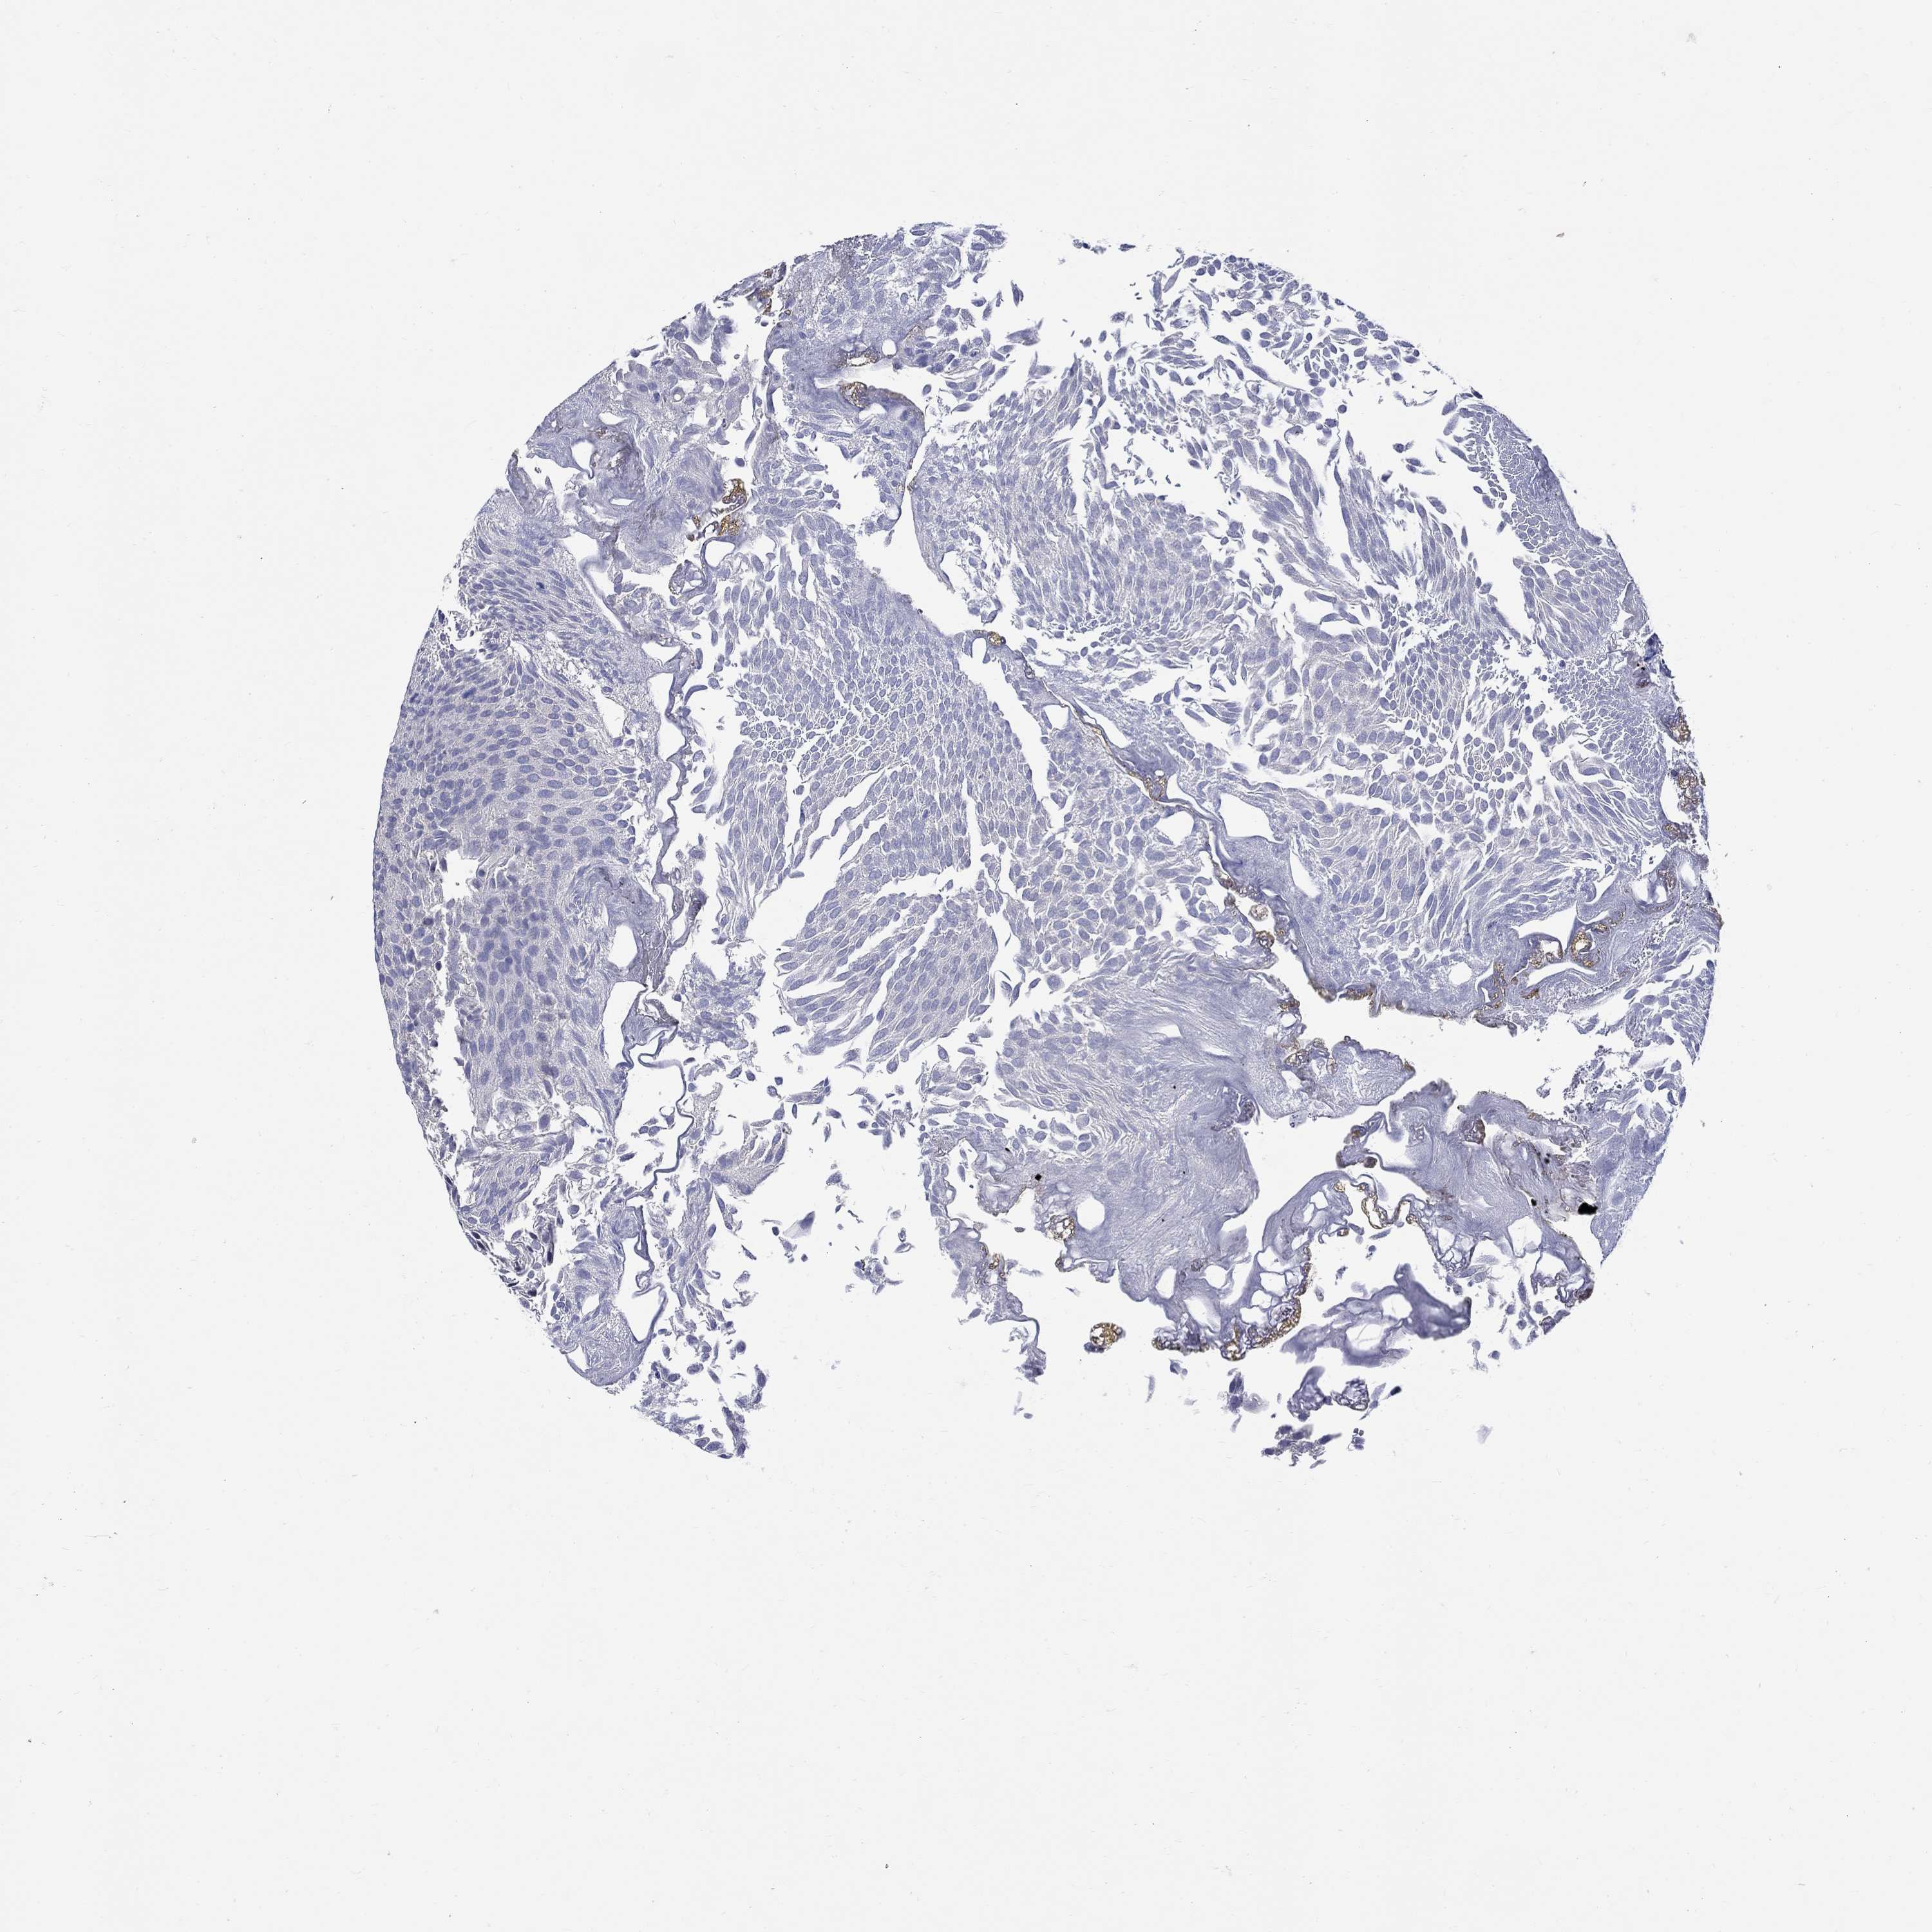

UROTHELIAL CANCER - Protein expressioni

A mouse-over function shows sample information and annotation data. Click on an image to view it in a full screen mode. Samples can be filtered based on level of antibody staining by selecting one or several of the following categories: high, medium, low and not detected. The assay and annotation is described here.

Antibody stainingi

Antibody staining in the annotated cell types in the current human tissue is reported as not detected, low, medium, or high, based on conventional immunohistochemistry profiling in selected tissues. This score is based on the combination of the staining intensity and fraction of stained cells.

Each image is clickable and will lead to virtual microscopy that enables deeper exploration of all samples and also displays staining intensity scores, fraction scores and subcellular localization as well as patient and tissue information for each sample.

Antibody HPA060505

Antibody HPA067637

Urothelial carcinoma, High grade

Urothelial carcinoma, Low grade

Urothelial carcinoma, NOS